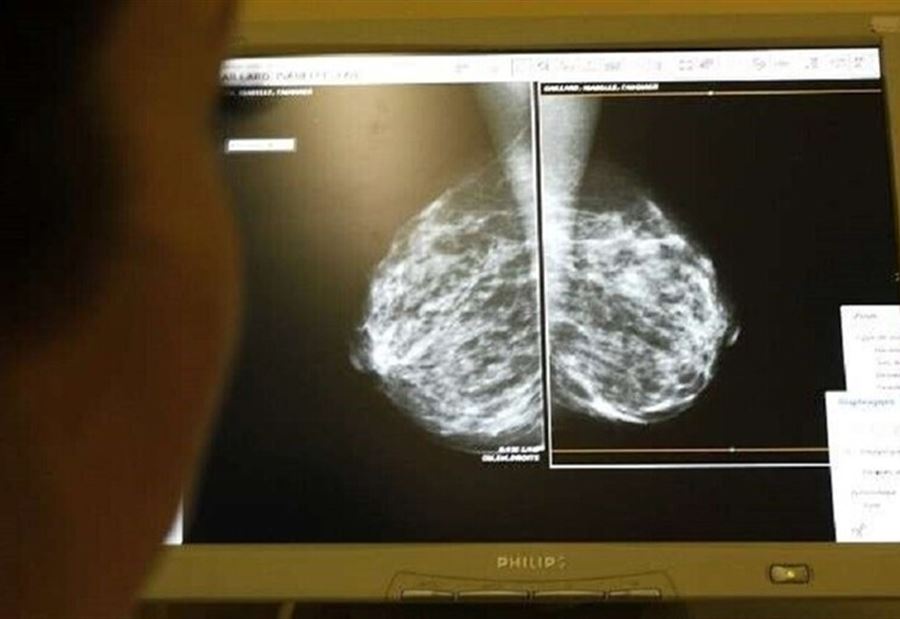

نظامٌ غذائيّ قد يَزيد من خطر إصابة النساء بـ"السرطان"

تشير أدلة جديدة إلى أن "الأنظمة الغذائية المليئة باللحوم المصنعة والزبدة والأطعمة المقلية والحلويات السكرية قد تزيد من خطر الإصابة بسرطان الثدي".